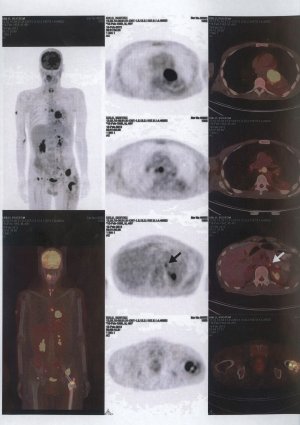

Pic 29

Pic 30

Bone scintigraphy is also a method that is used from time to time. Here, the bone content of the whole body is revealed. The purpose here is; It is to understand whether the mass has spread to other bones and to give an idea about whether the mass is benign or malignant (pic-29).

PET-CT, on the other hand, is a very advanced imaging method that is increasingly used today. It gives an idea about where there are masses in the body and whether they are good or bad (pic-30).